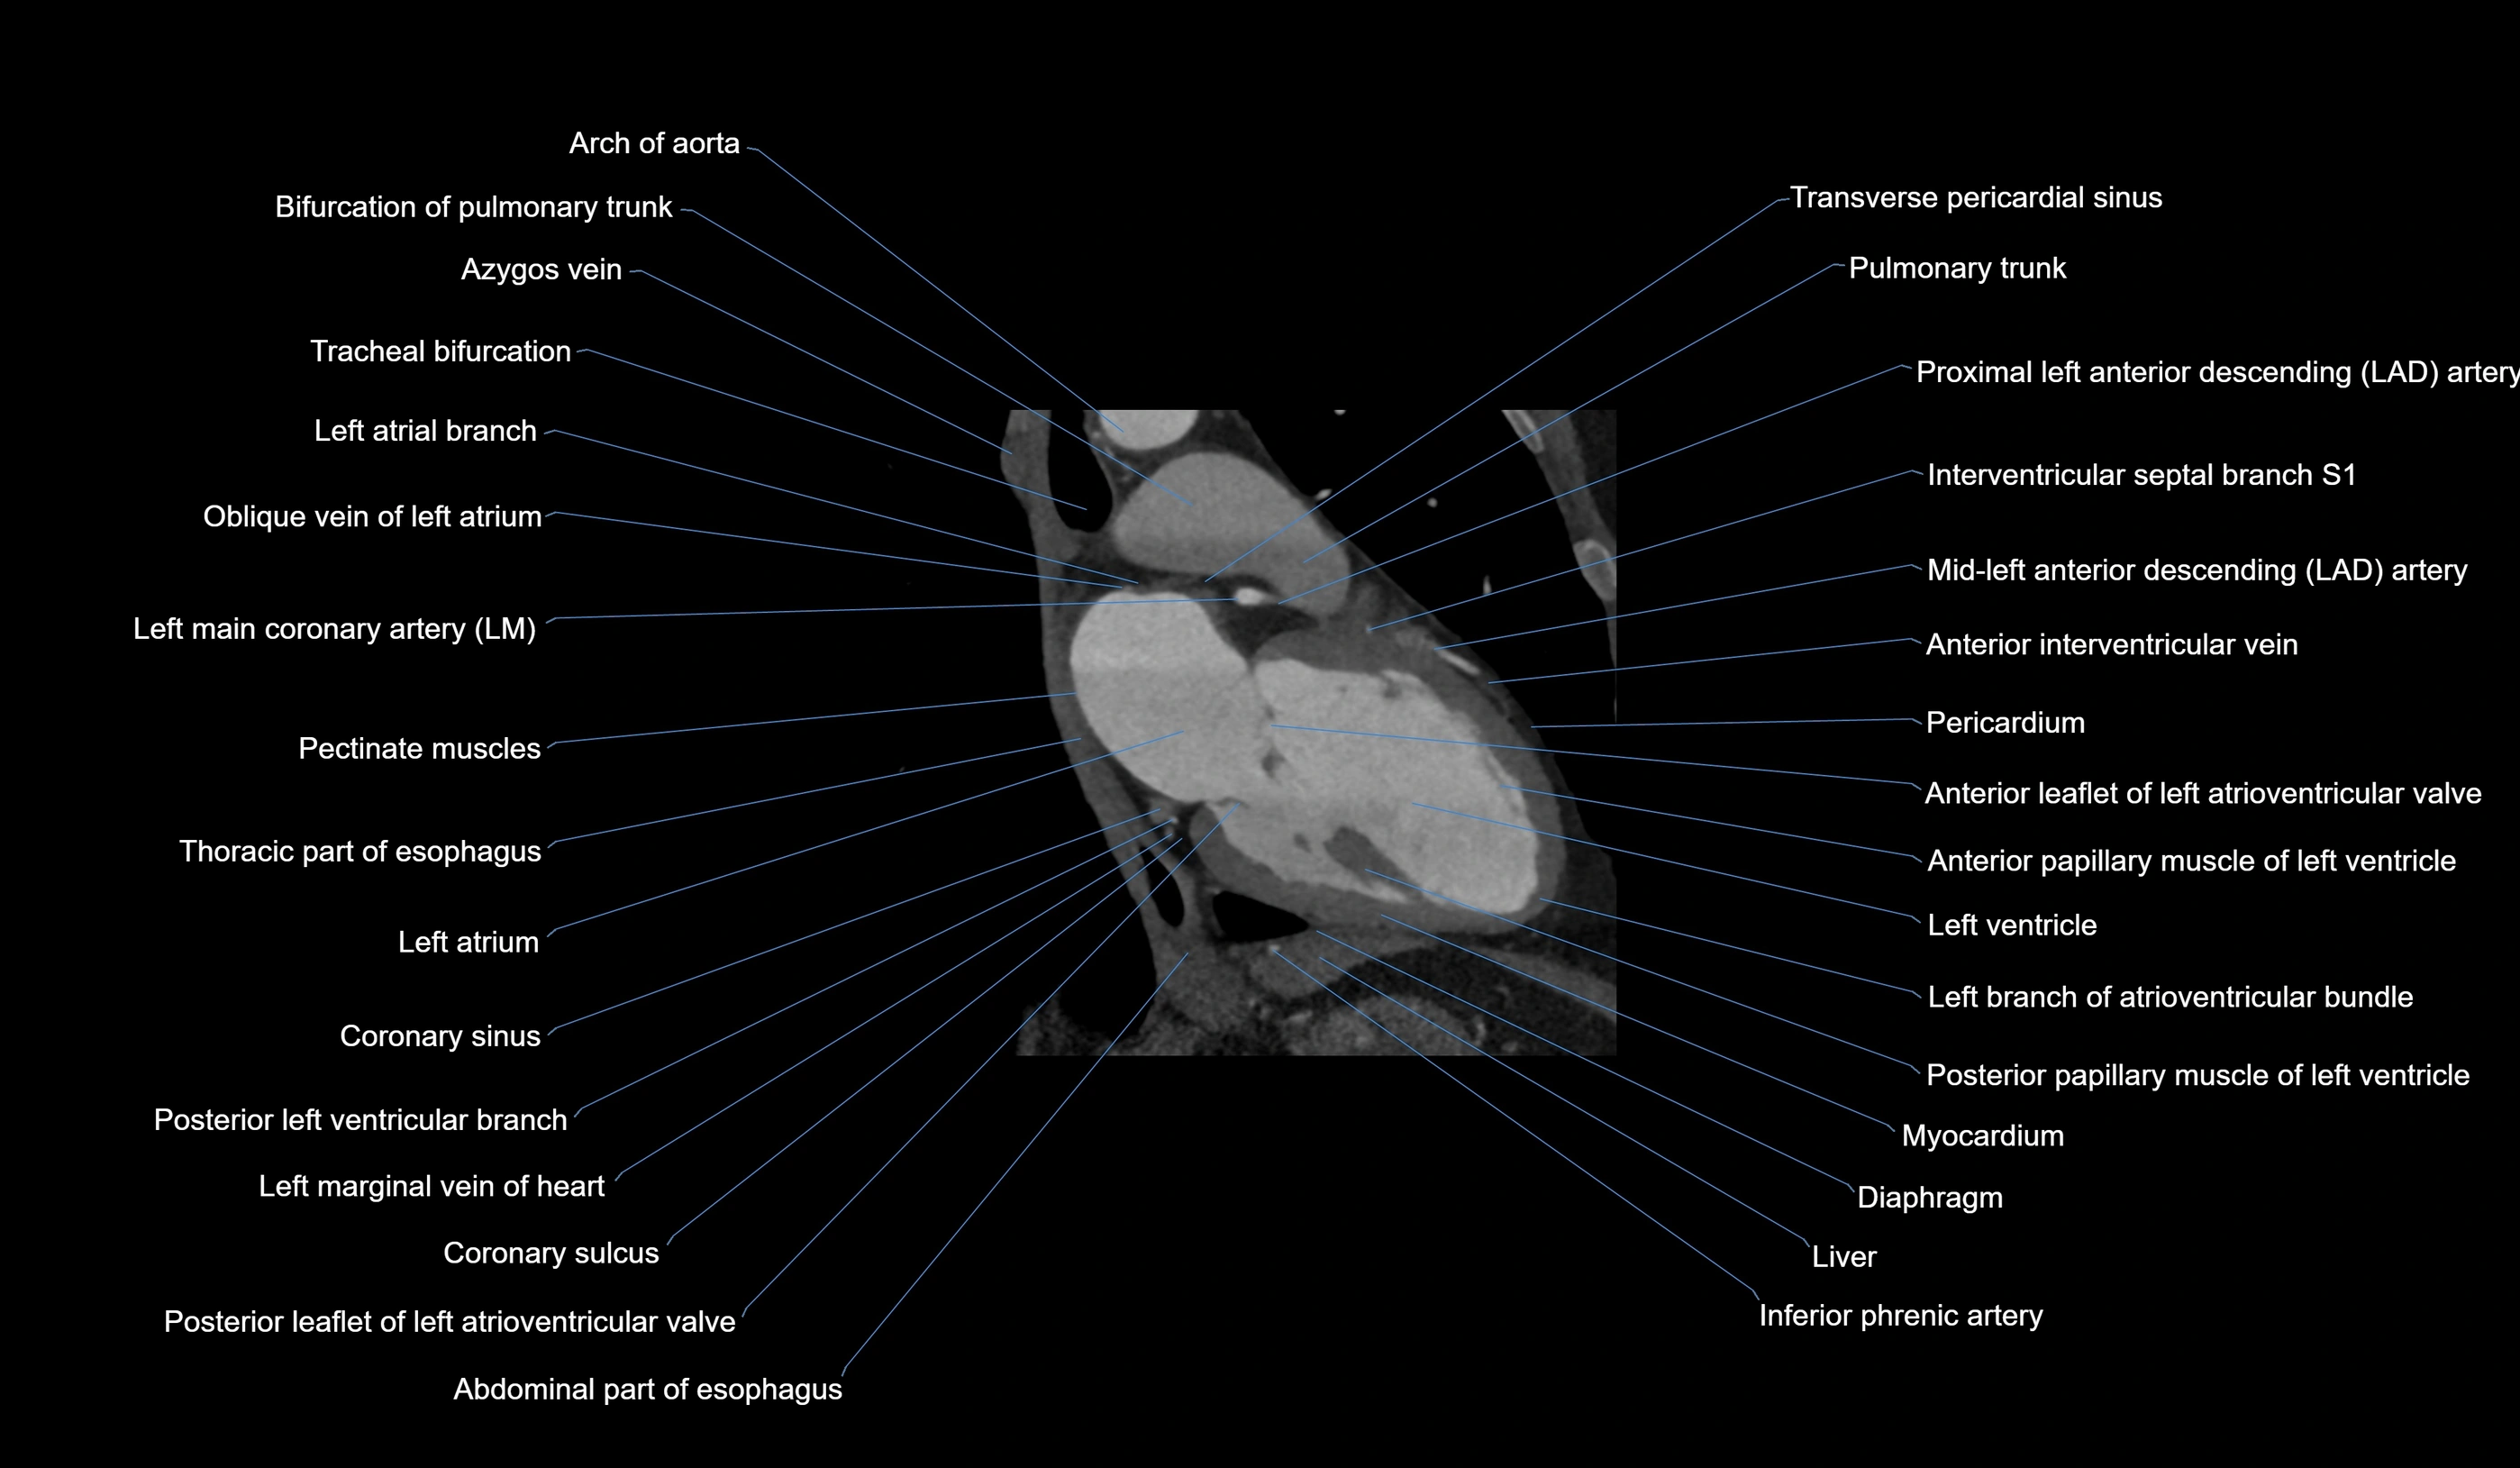

CT Appearance

CT Coronary Angiography (CCTA):

-

Best non-invasive modality for acute marginal artery visualization

Shows origin, course along the acute margin, and right ventricular branches

Detects stenosis, occlusion, calcified and non-calcified plaques, aneurysm, or anomalous course

Multiplanar reformats and 3D reconstructions help in pre-PCI and surgical planning

Critical for assessing right ventricular infarction risk in RCA disease

MRI image

CT images